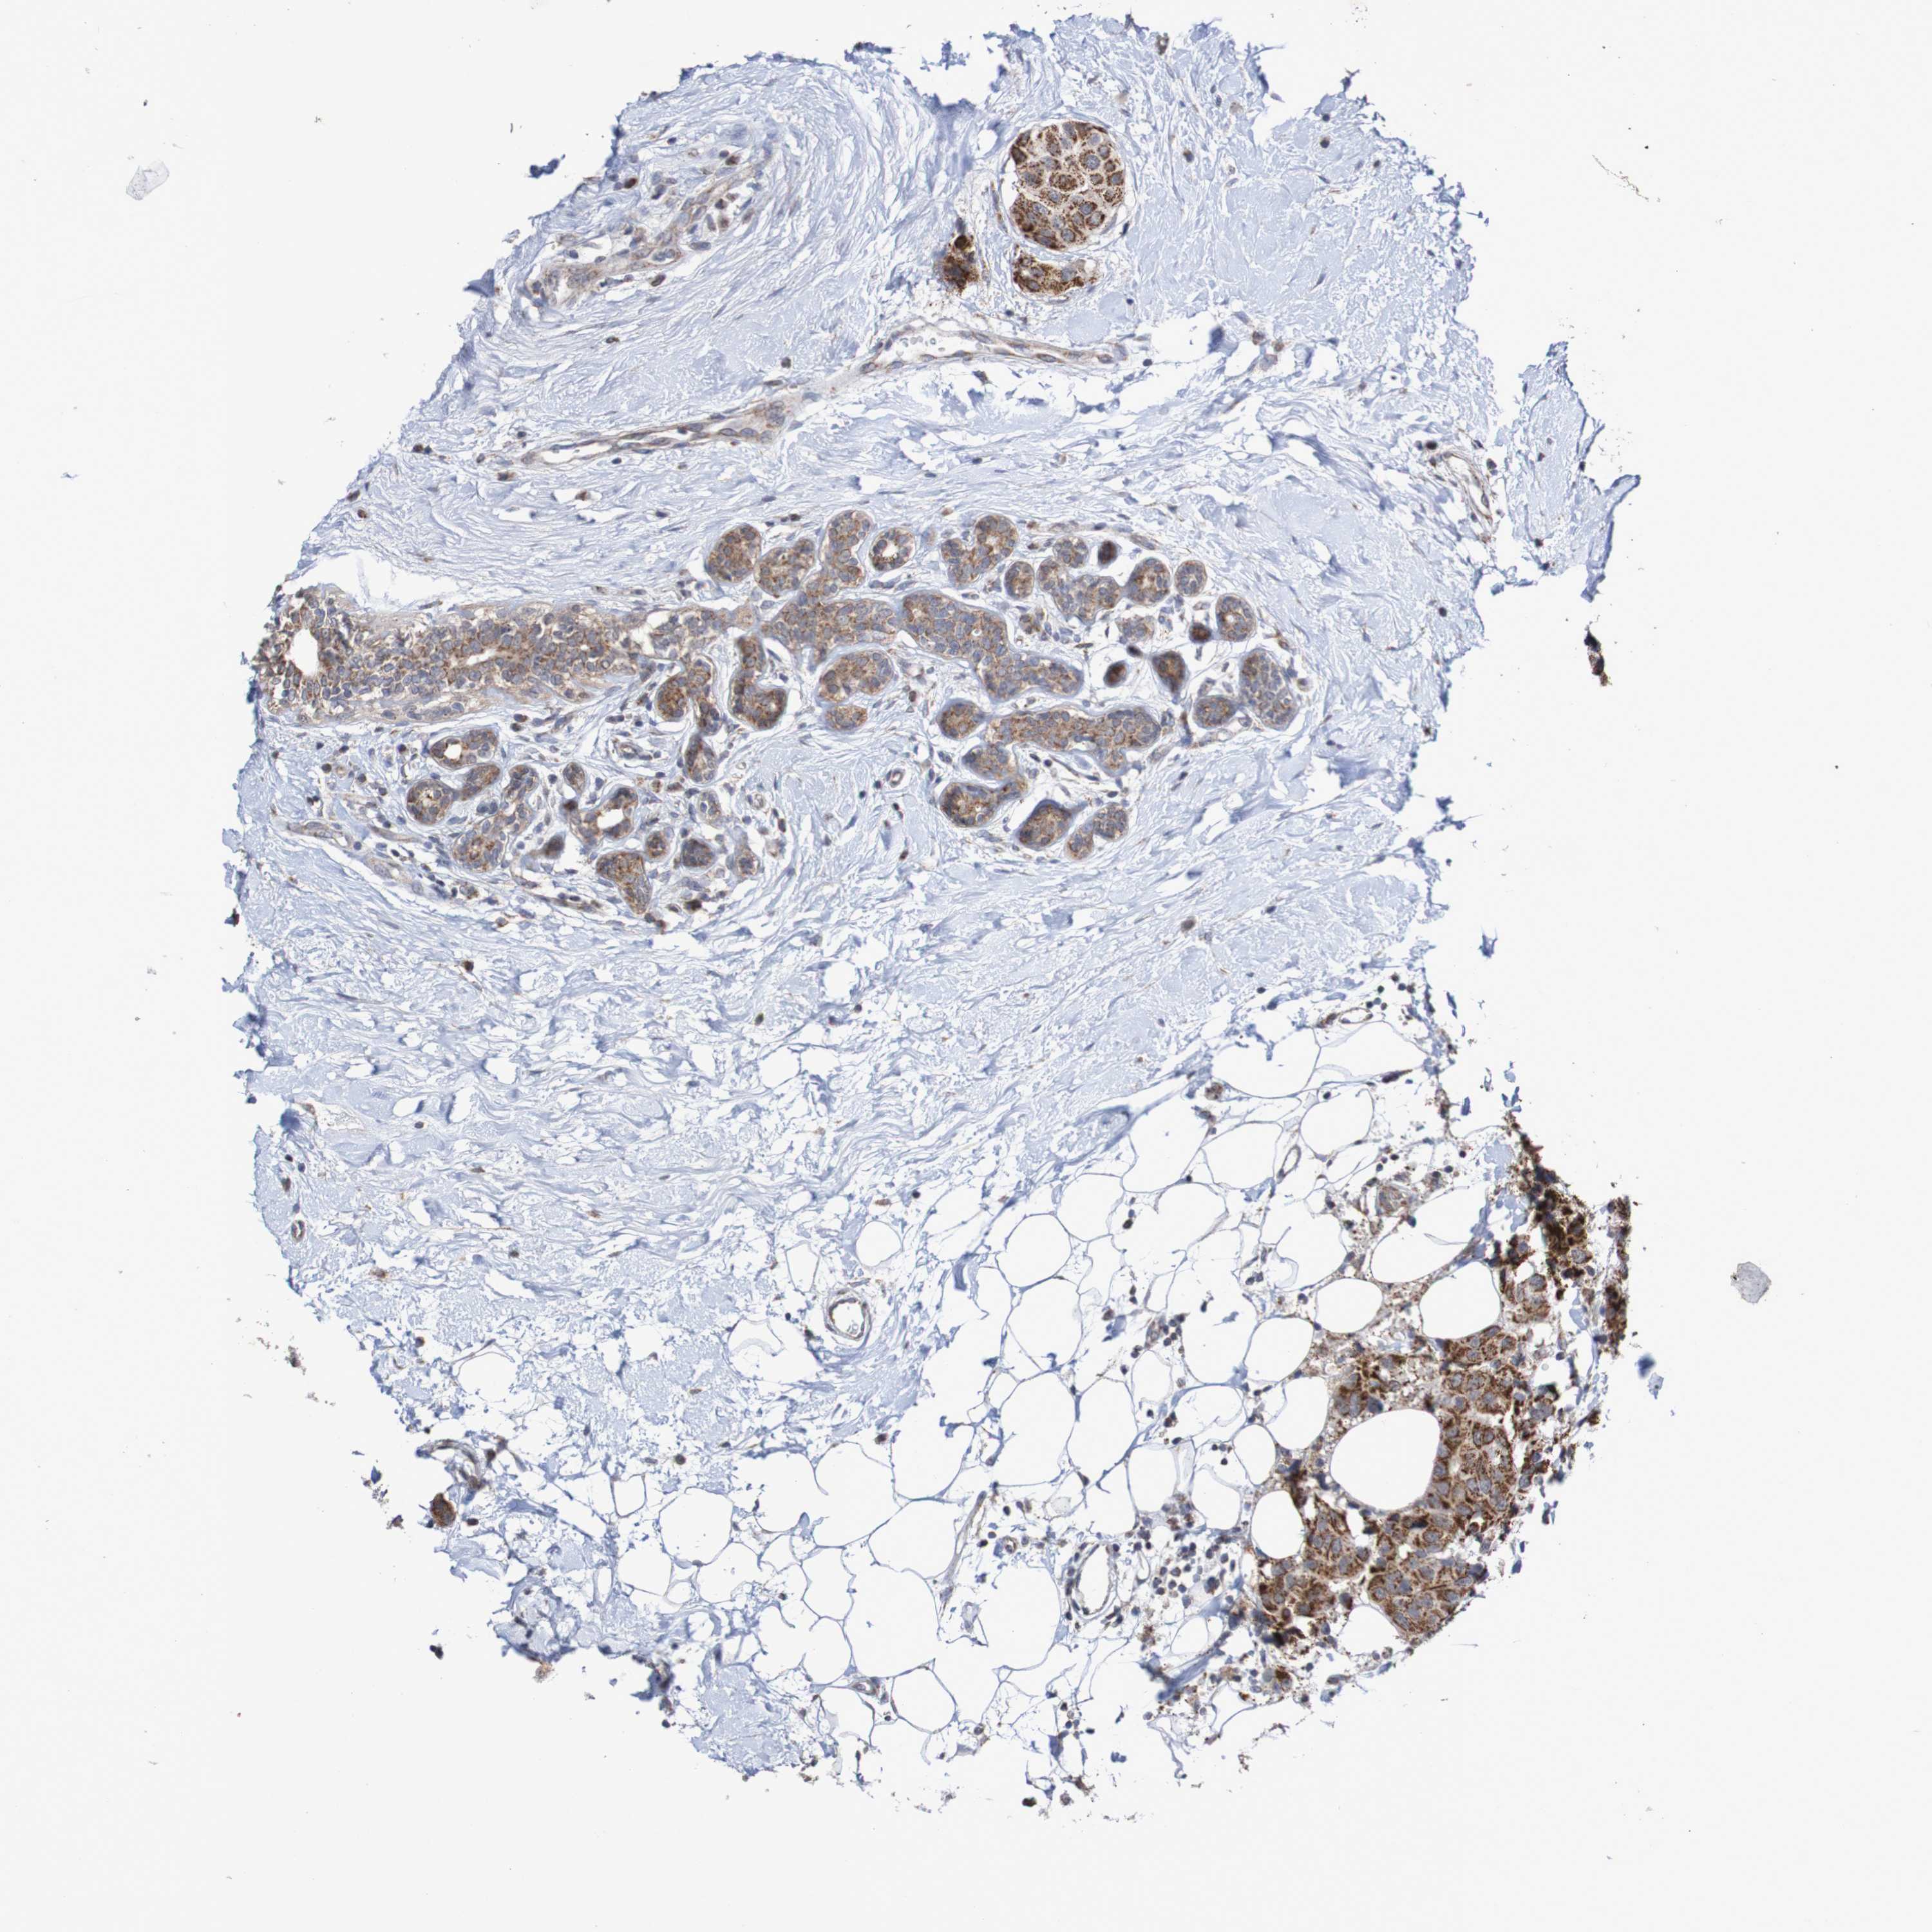

CANCER BREAST CANCER Show tissue menu

BRCA TCGA BRCA VALIDATION PROTEIN EXPRESSION